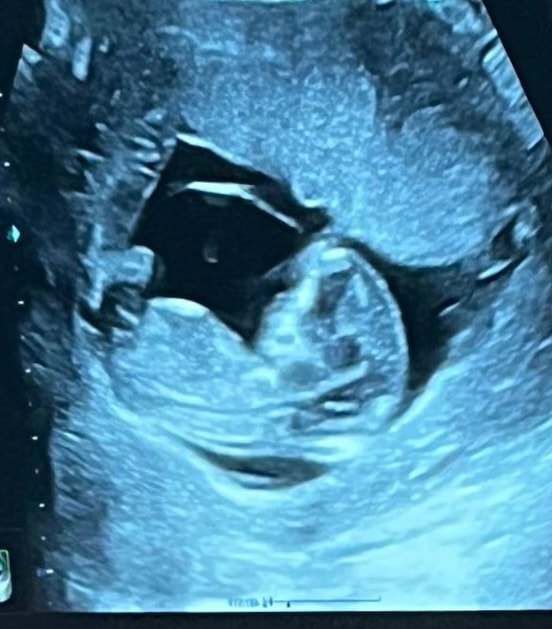

1 скрининг

Пол малышаТак надеялись хотя бы предположительно узнать пол, а врач сказала, что непонятно 🙃Может быть есть люди тут с пониманием, кто разбирается в наклоне полового бугорка и может подсказать 🥲 А где-то вычитала, что даже по форме черепа смотрят 😅